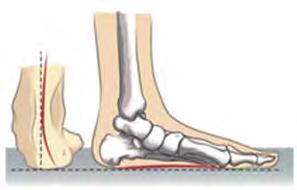

зупинити кровотечу, накласти стерильну пов’язку на рану, а потім знерухомити кінцівку. При закритому переломі знерухомлення кінцівки є першочерговим заходом. Варто зазначити, що у випадку всіх описаних травм необхідно обов’язково звернутися до лікаря. Спроба самостійного лікування може призвести до подальшого травмування організму. Порушення постави. Деякі проблеми опорно-рухової системи можуть розвиватися без зовнішніх впливів. Зокрема, часто трапляються порушення постави. Ви вже знаєте, що лордоз та

є

вигинами хребта. Їхнє посилення або згладжування може бути ознакою порушення постави. У випадку скривлення хребта вправо або вліво виникає сколіоз. Для профілактики порушень хребта необхідно зберігати правильне положення тіла під час сидіння за столом, правильно носити важкі предмети тощо (іл. 80). Поширеною формою порушення скелета є плоскостопість сплощення склепіння стопи (іл. 81). Воно супроводжується болем